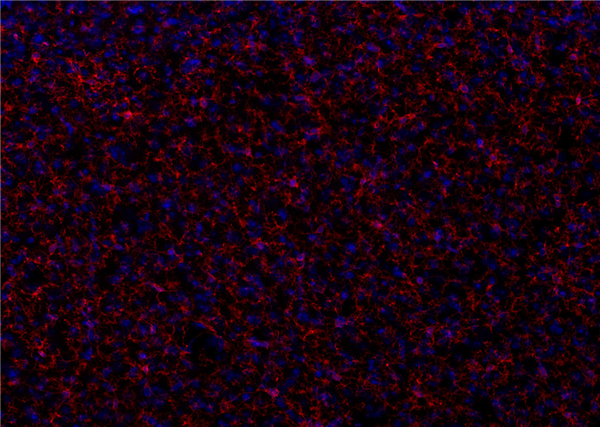

示例染色:使用兔抗P2Y12抗體(產(chǎn)品編號476 008,稀釋度1 : 500,紅色)對甲醛固定的鼠皮層切片進行間接免疫染色。細胞核通過DAPI染色顯示(藍色)。